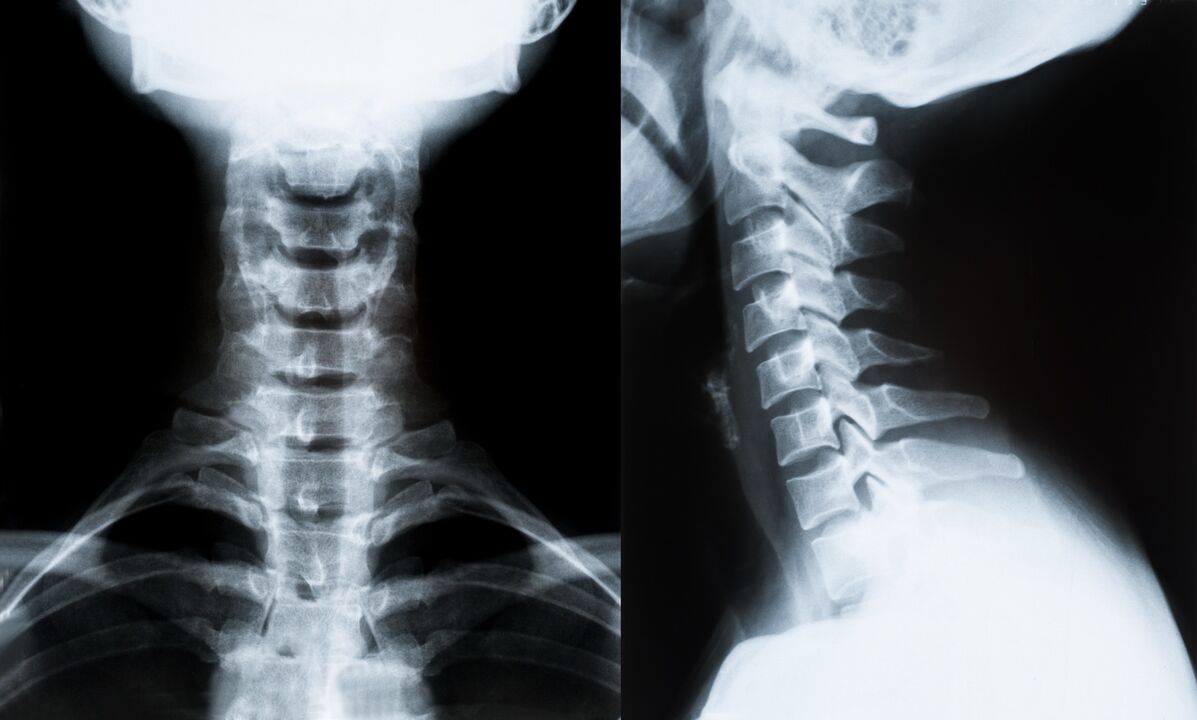

Les principales méthodes de diagnostic et de détermination ultérieure du traitement de l'ostéochondrose de la colonne cervicale :

- Radiographie. La méthode de diagnostic la moins efficace, mais traditionnelle.

- L'IRM est la méthode de diagnostic la plus efficace. Avec ce type d’examen du patient, toutes les structures nécessaires sont visibles.

- Si les changements doivent être mesurés, la tomodensitométrie est utilisée. Détermine la présence de hernies et d'autres choses.

- La dernière méthode est l’échographie duplex. Cette méthode de recherche détermine la vitesse du flux sanguin dans les artères.

Il est impossible de déterminer avec précision une maladie de la colonne vertébrale à la maison.